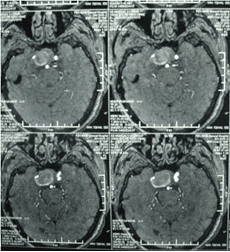

顱內(nèi)動脈瘤是指腦動脈的局部性異常擴(kuò)大,多在腦底動脈的分叉處或分支的夾角向外突出,多呈囊狀。TCD對顱內(nèi)動脈瘤的總檢出率為67 %,動脈瘤>1cm的檢出率為82 %。TC D 對較大動脈瘤的檢測有其特征性表現(xiàn),其典型表現(xiàn)為:瘤體內(nèi)血流速度明顯低于載瘤動脈血流速度,其收縮峰陡峭或多峰不整,舒張期末流速極低或斷流,PI 值增高,多為雙向血流,聲頻低鈍,似撞擊樣轟鳴音。

經(jīng)顱多普勒

頸內(nèi)動脈虹吸段巨大動脈瘤(約3cm ×3cm

TCD 檢查顱內(nèi)動脈瘤,可以了解動脈瘤部位,大小,瘤體內(nèi)血流,頻譜特征,脈動指數(shù),載瘤動脈血流速度等。其作為一種無創(chuàng)的腦血管病檢查手段,它摒棄了傳統(tǒng)腦血流圖的不準(zhǔn)確性和腦血管造影的有創(chuàng)性,亦為CT 、MRI 等現(xiàn)代影像技術(shù)提供了腦血管血流動力學(xué)參數(shù),成為影像診斷的重要佐證,利于病情隨診和篩選患者,因而對腦血管病診斷、療效評估有重要價值,也是腦血管病血流動力學(xué)研究不可缺少的設(shè)備之一。